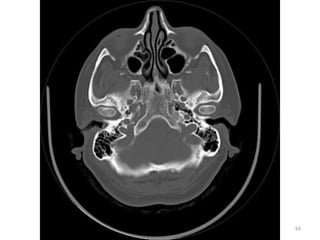

1. GLOBO OULAR (VITRIO)

2. FORAME MAGNUM

3. MUSCULO PITERIGÓIDE

MEDIAL

4. SEIO ESFENOIDAL

5. SEIO MAXILAR

6. ORELHA

1

2

3

4

5

6

ANATOMIA